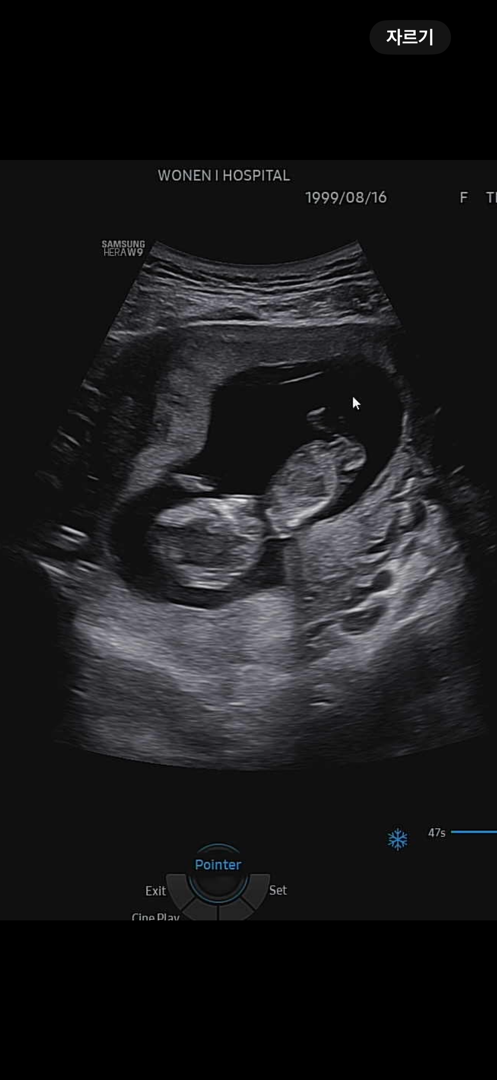

이들 ?? 딸?? 성별 봐주세요ㅠㅠㅠ

이걸로 보일까요?? 성별 고수님들 한번 봐주세요ㅠㅠ